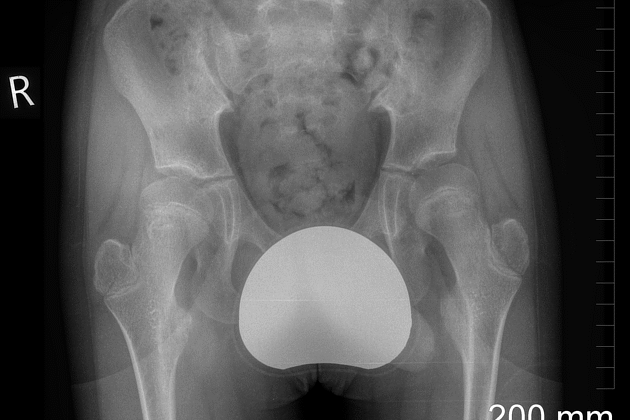

فعندما لا يتحرك مفصل الفخذ الأيمن بحرية كافية، يميل الحوض إلى أحد الجانبين. هذا الميل يجعل الساق اليمنى تبدو أطول من اليسرى، فيميل الجسم لتعويض الفرق في الطول. ومع الوقت يبدأ العمود الفقري في الانحناء للمحافظة على التوازن.

اختلاف بسيط في طول الساقين.

يميل الحوض تدريجيًا نحو الأعلى في جهة، وإلى الأسفل في الجهة المقابلة.

ينحني العمود الفقري جانبيًا ليحافظ على توازن الجسم.